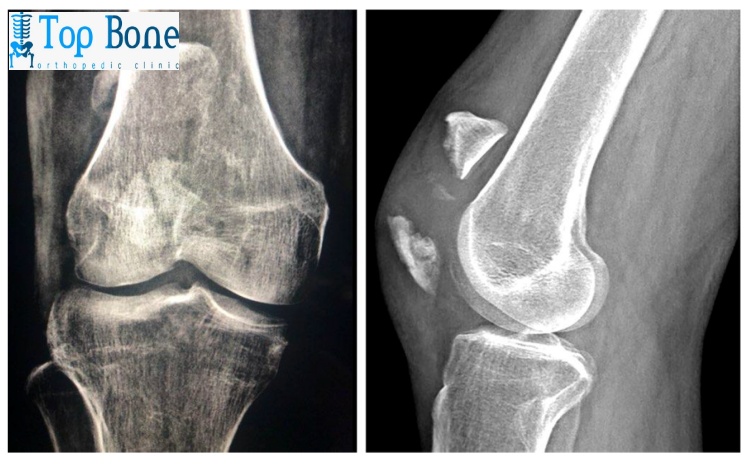

يقوم دكتور إبراهيم حسين أستاذ دكتور جراحة العظام و الإصابات و أستاذ جراحات العظام و اليد بكلية الطب جامعة الأزهر بتثبيت حالات الكسور والشروخ في جسم الإنسان بواسطة تركيب شرائح طبية ومسامير كما تساعد على التئام حالات الكسر بشكل طبيعي وفي مكانه الصحيح.

مما يضمن للمريض الحرص على استعادة حياته اليومية بهذا الشكل السريع وبدون ألم كما تناسب هذه الشرائح والمسامير بصفة خاصة حالات الكسور القريبة من المفاصل ويتقبل جسم الإنسان هذه الشرائح والمسامير بشكل عادي فلا يعتبرها جسم غريب عنه أو يرفضها، وذلك لأن هذه الشرائح هي مصنوعة من عدة سبائك وهي:

- حالات المصابة بالكسر الذي يشتمل على فتات عظام وشظايا كثيرة حيث يتطلب إلى تنظيف وإزالة لتلك الأجزاء التالفة بعد ذلك العمل على تثبيت العظام من أجل الالتئام وهذا لا يتم إلا من خلال الجراحة.

- في حال إذا كان الكسر الحادث في العظام يقع في جهة قريبة من المفصل وقد ينال هذا الضرر من المفصل أيضًا.